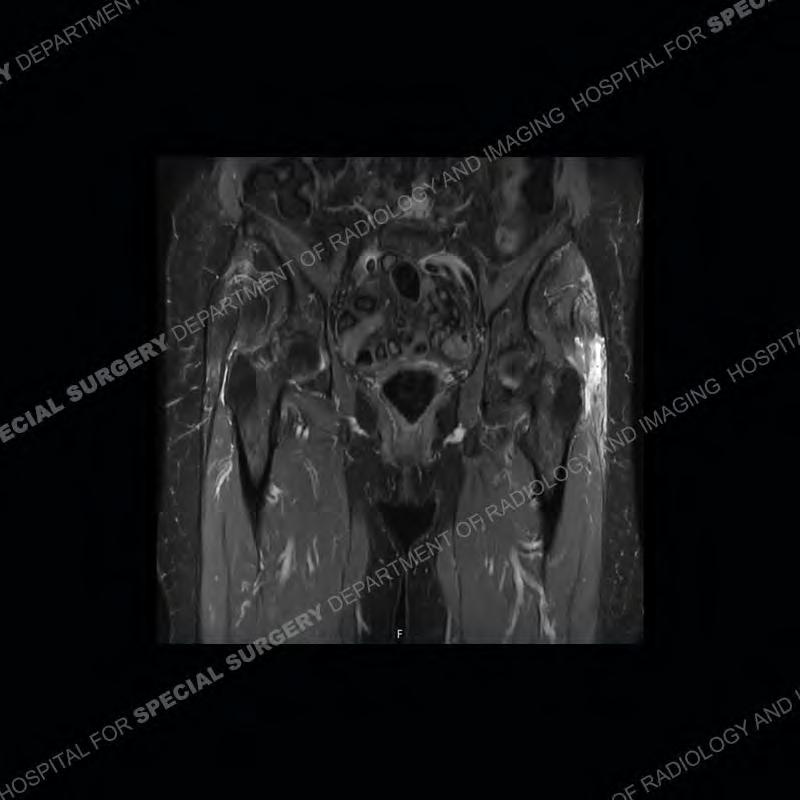

The radiograph is not particularly contributory in this case. The MRI demonstrates markedly abnormal architecture of the gluteus minimus and anterolateral band of the gluteus medius. Portions of the tendons are high signal, portions are highly attenuated, and portions are disrupted. A large, complex fluid collection is present in the adjacent soft tissue.

Diagnosis: Gluteal Tendinosis and Disruption with Complex Trochanteric Bursal Collection

Not as much of a diagnostic dilemma as many of the other cases shown but just a nice example of the pathology seen of the gluteal tendons and a cause of trochanteric pain. Although, frequently thought of in isolation, trochanteric bursitis or bursal thickening is much more commonly a reactive change to underlying pathology of the subjacent gluteal tendons. The gluteus medius is divided into a posterior band and an anterolateral band. Tendinosis and partial tearing very commonly will involve the gluteus minimus and especially the more posterior fibers and then propagate into the anterior lateral band of the gluteus medius. Involvement of the posterior band of the medius is much less common and engenders a marked degree of functional impairment.

The bursae about the greater trochanter can be a little bit confusing especially given the terminology. Trochanteric bursitis is implied to mean the subgluteus maximus bursa which is present deep to the maximus and just lateral/superficial to the trochanter. That is the bursa involved in this case. In this case the complexity of the bursa relates to the tendon tearing with inflammatory change and probably hemorrhage accounting for the complexity. Two other, less frequently involved bursa are also present. The subgluteus medius and subgluteus minimus bursa are found just deep to the named tendons. Although pathology does frequently follow the previously described pattern it is possible to have isolated pathology to either the medius or minimus.